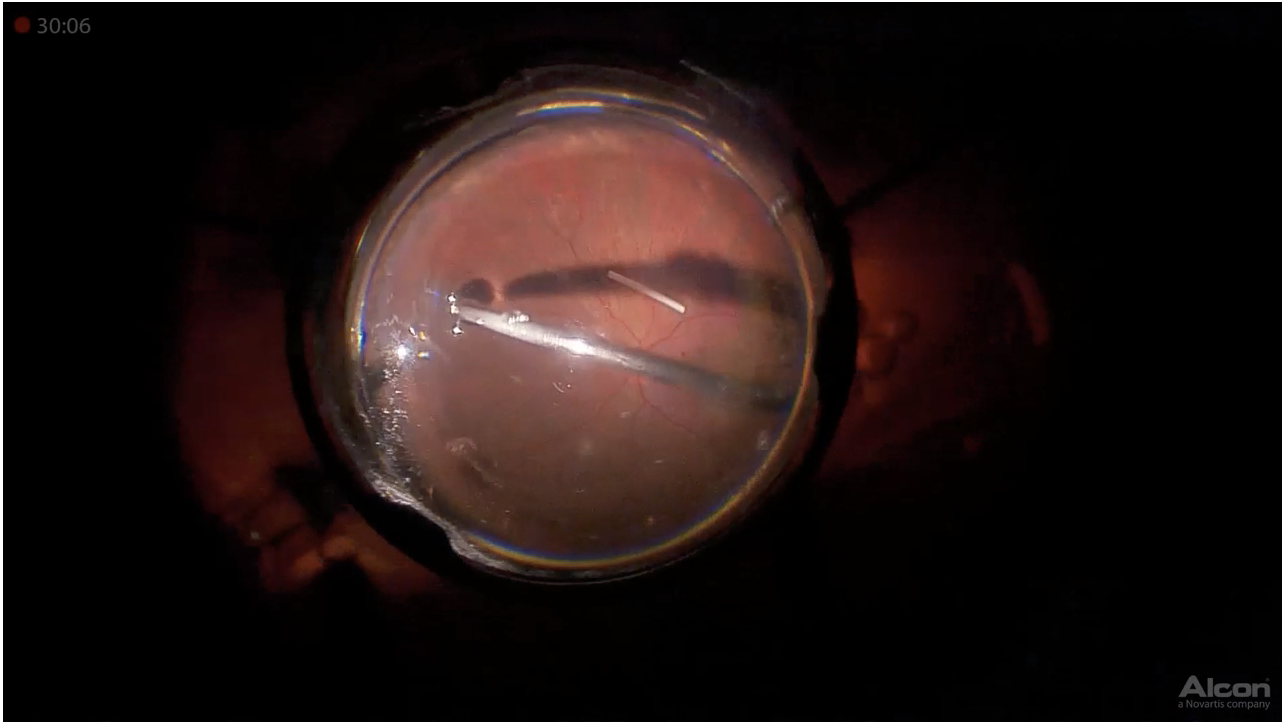

Formula Retina 3D

A panel discussion course in which leading retina specialists share how they manage various medical and surgical conditions, featuring 3D videos.